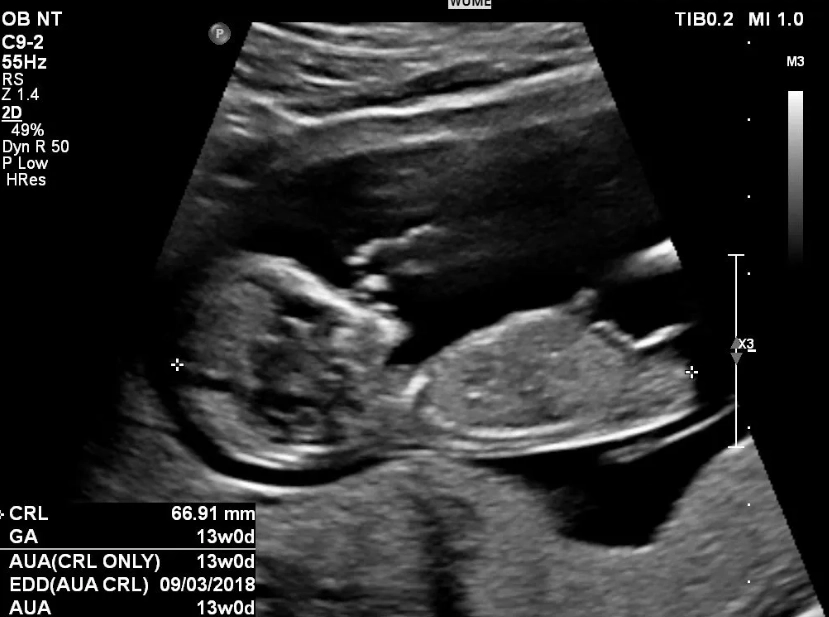

What Really Happens at Your 12-Week Ultrasound?

Forget the month debate. The 12-week scan is where the magic—and the medicine—happens. This is often the first detailed look at your baby, and the emotional impact is huge. It's not just a blurry blob anymore.

This is the core of the 12-week ultrasound. The sonographer takes a very precise measurement of the fluid-filled space at the back of your baby's neck. This is the nuchal translucency. All babies have some fluid there, but an increased measurement can be a soft marker for certain chromosomal conditions, like Down syndrome (Trisomy 21).

The "Wow" Factor: What You'll Actually See

While the tech is taking measurements, you'll get to watch. At 12 weeks, your baby looks undeniably human.

First, it confirms your due date with much greater accuracy. Early ultrasounds (before 14 weeks) are the gold standard for dating a pregnancy. They measure the baby from crown to rump (CRL). If this measurement differs by more than 5-7 days from your LMP date, your due date will be officially changed. I've had my own due date adjusted by 5 days based on this scan—it's incredibly common, especially if your cycles aren't a perfect 28 days.